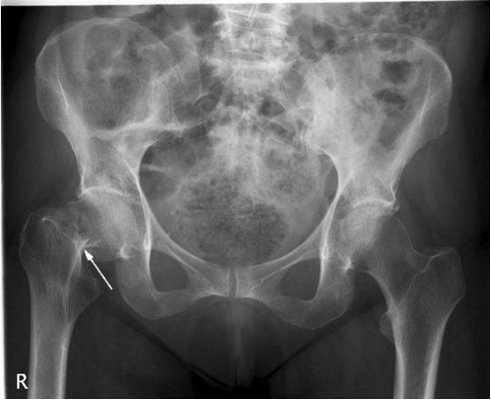

Передне-задняя рентгенограмма таза. Обратите внимание на непрерывность второй крестцовой и пограничной линии. Нарушение этой непрерывности является признаком нарушения соосности. Подвздошный гребень проходит от задней верхней подвздошной ости к передней верхней подвздошной ости. Передне-задняя рентгенограмма тазобедренного сустава: надвертлужный сегмент подвздошной кости над сводом вертлужной впадины. Тонкая медиальная стенка вертлужной впадины накладывается на подвздошно-седалищную линию. Фигура слезы расположена у нижнего отдела медиальной стенки. Под «бровью» подразумевается кортикальное уплотнение свода вертлужной впадины. Рентгенография таза в проекции входа выполняется для оценки передне-задней соосности. Ветви лобковой кости почти перекрывают друг друга. Нижняя ветвь расположена несколько кзади относительно верхней. Хорошо визуализируются передняя и задняя подвздошные ости, между которыми лежит подвздошный гребень. Передний край крестцово-подвздошного сустава проецируется кнаружи от заднего края по причине косого расположения сочленения. Рентгенография таза в проекции выхода выполняется для оценки верхней и нижней соосности таза. Запирательное отверстие имеет вид «глаза совы». Рентгенограмма в проекции выхода обычно позволяет получить наилучший снимок для оценки невральных отверстий крестца. Подвздошная (левая задняя) косая рентгенограмма левого тазобедренного сустава является запирательной косой рентгенограммой правого тазобедренного сустава. С левой стороны хорошо визуализируются задняя (подвздошно-седалищная) колонна и передний край вертлужной впадины. Запирательная (левая передняя) косая рентгенограмма левого тазобедренного сустава (подвздошная косая рентгенограмма правого тазобедренного сустава). На этом снимке передняя или подвздошно-гребешковая колонна вертлужной впадины отображена в профиль. Хорошо визуализируется задний край вертлужной впадины. Рентгенография тазобедренного сустава в боковой проекции (боковая горизонтальным пучком или боковая по Johnson) наиболее часто выполняется при подозрении на перелом или для оценки поворота вертлужной впадины после тотального эндопротезирования тазобедренного сустава. Задний отдел тазобедренного сустава идентифицируется по выстоянию седалищного бугра. Боковая рентгенограмма тазобедренного сустава в положении «ноги лягушки»: передне-наружное укорочение головчато-шеечного перехода. Большой вертел накладывается на шейку бедренной кости. Шейка и диафиз бедренной кости ориентированы по одной линии. Рентгенография левого тазобедренного сустава в косой проекции была выполнена у пациента в положении стоя с задним разворотом примерно на 65°. Этот снимок демонстрирует покрытие переднего отдела головки бедренной кости, строение свода вертлужной впадины и переднего отдела головчато-шеечного перехода. Малый вертел развернут анфас и отчетливо не различим. Шейка бедренной кости в положении антеверсии по отношению к телу бедренной кости. Передне-задняя рентгенограмма крестцово-подвздошных сочленений. Два суставных края визуализируются в нижних 2/3 каждого из суставов, что отражает косую направленность сочленений от заднемедиальной к передне-латеральной поверхности. Верхняя 1/3 сустава представлена, в основном, синдесмозом и имеет положение, близкое к корональному. Заднепередняя рентгенограмма крестца в проекции Ferguson: передний и задний края суставов визуализируются в виде одной линии, что обусловлено направлением рентгеновского пучка. Легко просматриваются невральные отверстия. Дугообразные линии представляют собой верхние края невральных отверстий. На левой задней косой (правой передней косой) рентгенограмме правый крестцово-подвздошный сустав отображается в профиль, а суставные поверхности контурированы. Хрящ более толстый на подвздошной стороне сустава, поэтому ранние признаки сакроилеита будут определяться при рентгенографии на подвздошной стороне.

Рисунок 1. Рентгенограмма таза в передне-задней проекции. Рисунок 2. Рентгенограмма в боковой проекции при «позе лягушки» - бедро в положении 45° сгибания и максимальной наружной ротации. Рисунок 3. Рентгенограмма тазобедренного сустава в переднезадней проекции.

Снимок 1. На этом рентгеновском снимке изображен здоровый тазобедренный сустав. Мы можем здесь увидеть:

- правильную округлую форму головки бедренной кости;

- нормальных размеров суставную щель, т. е. достаточное расстояние между головкой бедренной кости и сочленяющейся с ней вертлужной впадиной.

Здоровый тазобедренный сустав. Фотография из архива доктора Евдокименко

Тем не менее этому пациенту почему-то поставили диагноз «коксартроз второй стадии» и приговорили к операции по замене сустава.